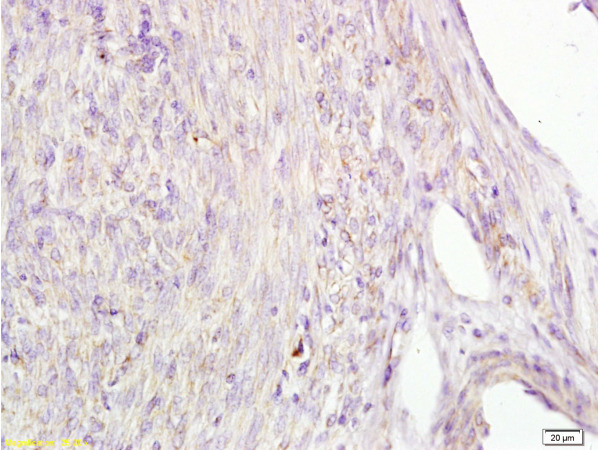

IHC-P analysis of human cervical carcinoma tissue using GTX60214 Alpha fetoprotein / AFP antibody [A2].

Dilution : 1:100